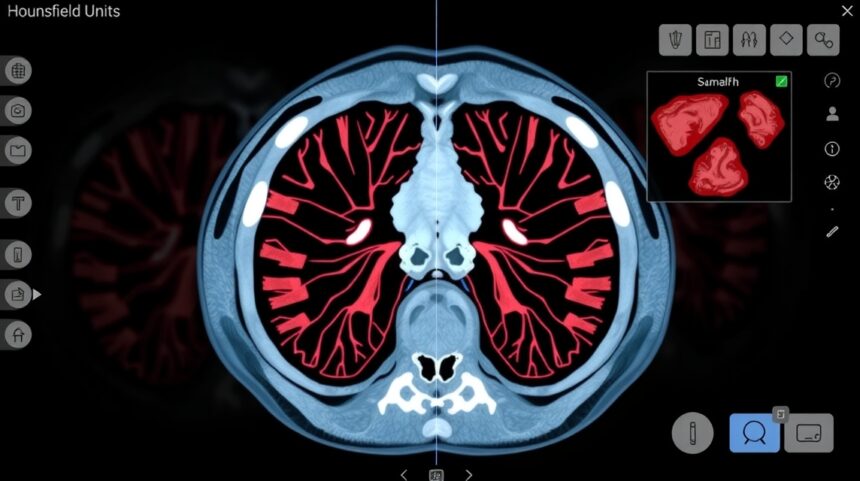

A gyakorlatban ez azt jelenti, hogy amikor egy CT-készülék átvilágítja a testünket, minden egyes apró területre (pixelre) kiszámít egy Hounsfield-értéket. Ezek az értékek aztán különböző szürkeárnyalatokká alakulnak át, amelyekből összeáll a végső CT-kép.

A sűrűbb és nehezebb anyagok több röntgensugarat nyelnek el, míg a könnyebb, levegővel teli területek szinte akadálytalanul engedik át őket. A CT-készülék detektorai pontosan mérik ezeket az intenzitásváltozásokat, és matematikai algoritmusok segítségével alakítják át őket Hounsfield-értékekké.

Ez a folyamat rendkívül gyors és precíz – másodpercek alatt több ezer mérési pont adatait dolgozza fel a gép. A végeredmény egy háromdimenziós térkép, ahol minden pont egy konkrét Hounsfield-értékkel rendelkezik, amely pontosan tükrözi az adott terület fizikai tulajdonságait.

A Hounsfield-skála értékei és jelentésük

Negatív tartomány: -1000 HU és 0 HU között

🫁 Levegő (-1000 HU): A skála alsó végpontja, ahol gyakorlatilag nincs röntgensugár-elnyelés

💨 Tüdőszövet (-950 HU és -500 HU között): A levegővel teli alveolusok miatt alacsony értékek

🧈 Zsírszövet (-200 HU és -50 HU között): Könnyű szerves anyag, amely kevés sugárzást nyel el

Pozitív tartomány: 0 HU felett

A pozitív Hounsfield-értékek a víznél sűrűbb anyagokat jelölik. Itt találjuk a legtöbb emberi szövetet és szervet, amelyek különböző mértékben nyelik el a röntgensugárzást.

Lágyrészek (0-100 HU között):

- Izomszövet: 10-40 HU

- Májszövet: 40-60 HU

- Veseszövet: 30-50 HU

- Agyállomány: 20-40 HU

Sűrűbb szövetek (100 HU felett):

- Csontszövet: 700-3000 HU

- Kontrasztanyaggal telített területek: 100-500 HU

- Fémimplantátumok: 1000-4000 HU